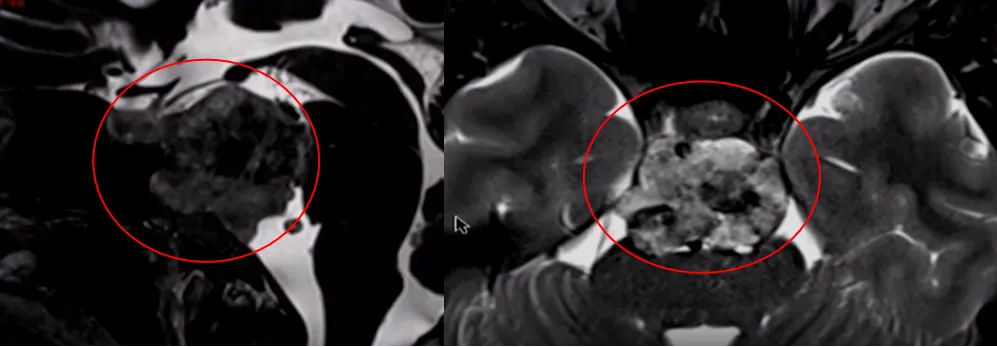

这是一个非常具有挑战性的脊索瘤,因为它渗入了基底动脉的血管壁,以及基底动脉的大部分分支。肿瘤纤维化程度很高,正如磁共振弥散成像显示的。基底动脉是位于脑干腹侧的一条重要血管,由左右两条椎动脉在颅腔内汇合形成,向上延伸并分出大脑后动脉等分支,主要负责为脑干、小脑、丘脑及部分大脑输送血液和氧气,是维持生命中枢功能的关键血管。

基底膜完全被肿瘤包裹和阻挡,因此福教授术中花了很长时间才把这些分支从肿瘤中分离出来。

在这里,福教授使用了“筷子技术”,在狭窄的通道里,可以有足够精准的操作来做到这一点。在这种情况下,福教授只使用了一块脂肪来完成闭合,填塞脂肪后,患者术后可以很快就坐起来。福教授认为其中一个诀窍就是在手术后让病人尽可能快地保持直立的姿势,以降低颅内压。

借助角度镜的广阔视野、成角器械的灵活操控,以及内镜医生那双极其灵巧而技术精湛的手,经鼻内镜手术正不断带来惊喜。